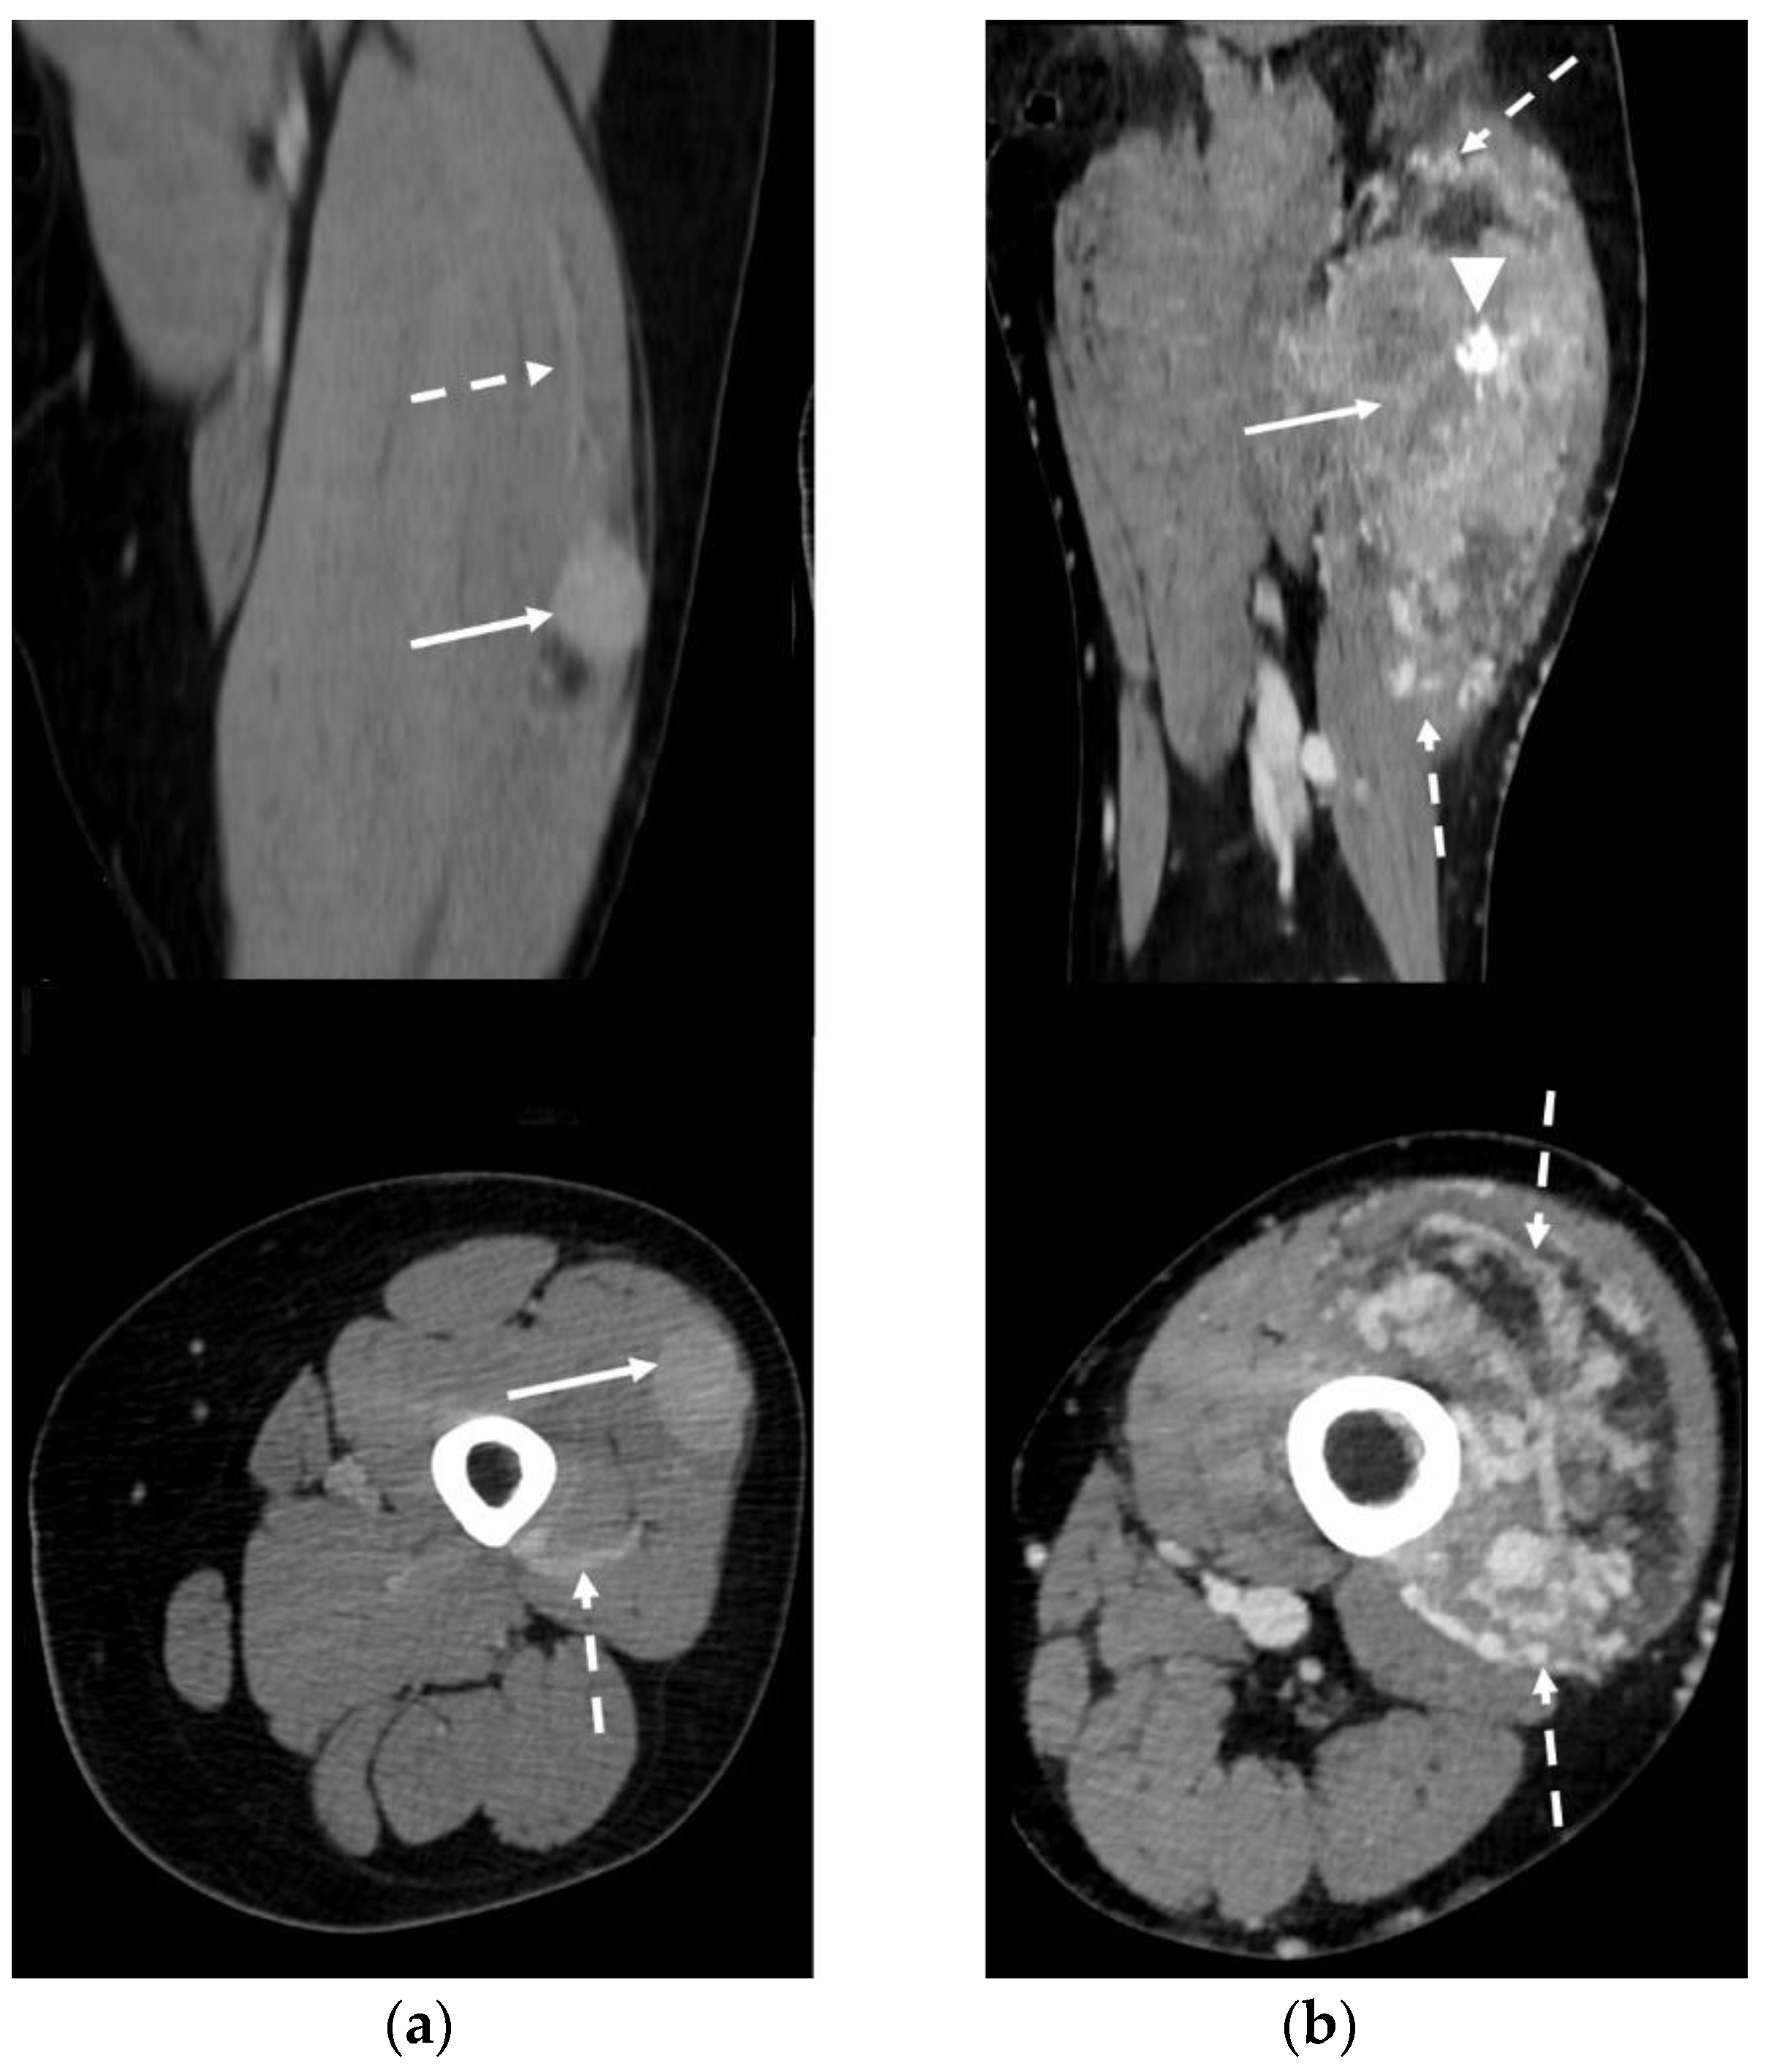

3.5. CT Features